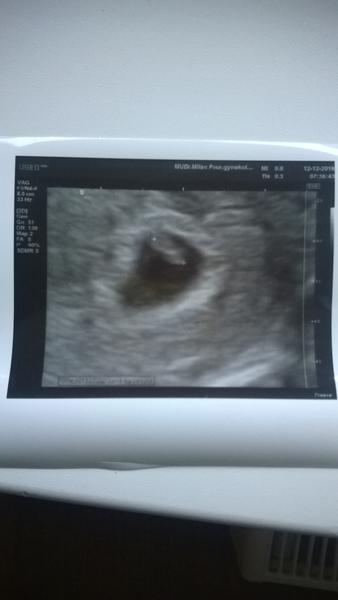

@katiex tady je moje ,,vysoká sliznice,, 🙂 v 6tt 🙂 ... taky se netvářili moc nadějně a přece to dobře dopadlo ... tehdy mi dokonce řekl že spíš příjde MS a navíc vzhledem k mé cukrovce to nevidí optimisticky a přece se zadařilo 🙂 malá má aktuálně 3,5 měsíce ... a loni touhle dobou už byla malá fazolka 🙂

Ahojky, tak jsem dnes byla na kontrole, z vysoké sliznice je 5mm miminko a tluče mu srdíčko 💕. Odpovídá o týden mladší, ale zahnízdilo až 10dpo, takže jsem s tím počítala. Moc děkuji za podporu 🍀

@katiex perfektni! 🙂 Ja jdu pozitri, tak snad budu mit podobne krasnou fotku 🙂 ❤

@katiex zapomnela jsem napsat 🙂 minulou stredu uz i u nas bylo srdicko a 7 mm embryjko, podle doktora odpovidalo 6 + 4 (vic nez o dva tydny mene, nez podle ms, ale pry nic neobvykleho, rozhozeny cyklus po vysazeni HA). Takze hura a snad to bude u nas obou zdarne pokracovat 🙂